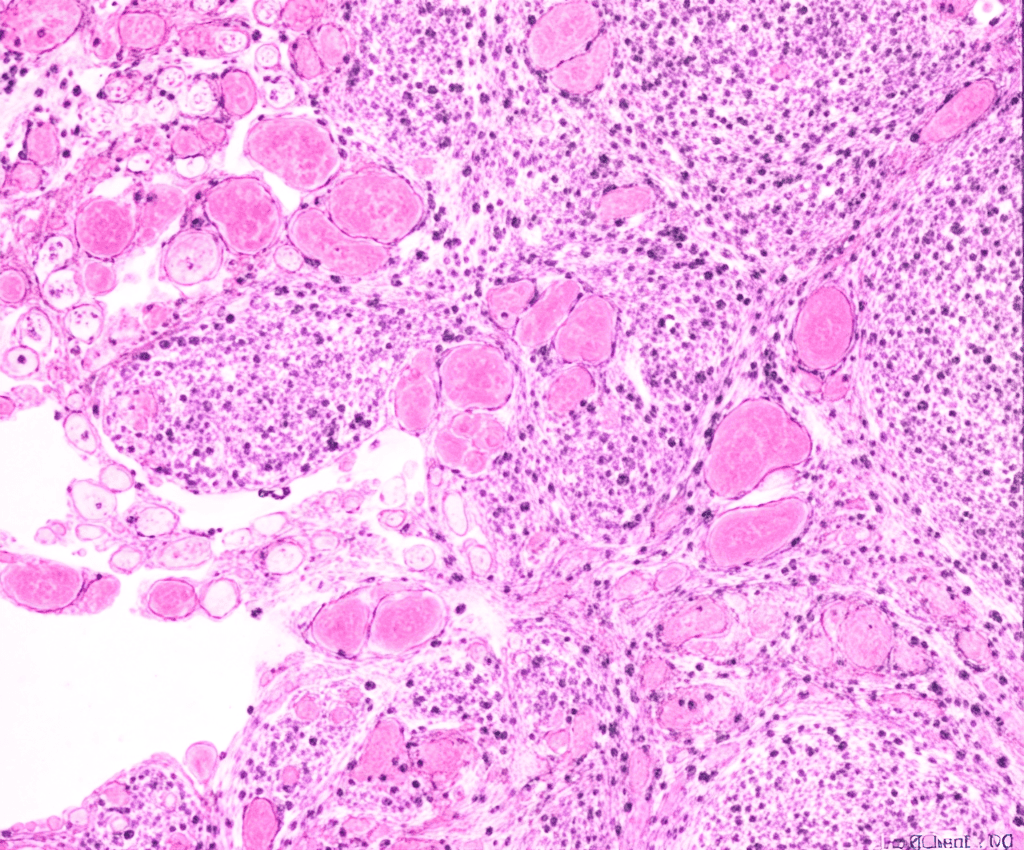

O serviço atua de forma integrada a todas as especialidades médicas, realizando exames histopatológicos, intraoperatórios, imuno-histoquímica, hibridação in situ e patologia molecular, fundamentais como fatores preditivos.